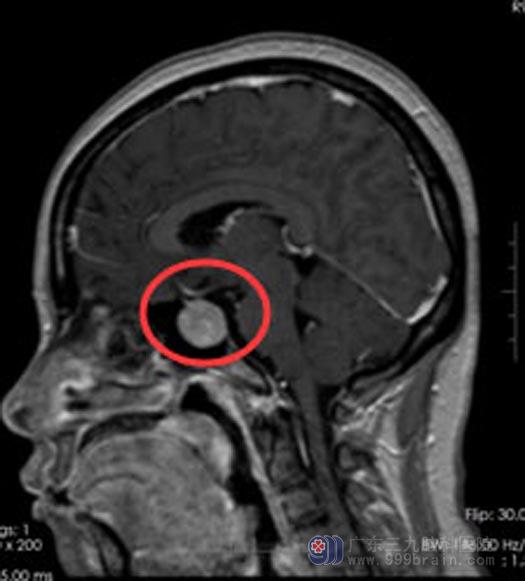

手术前